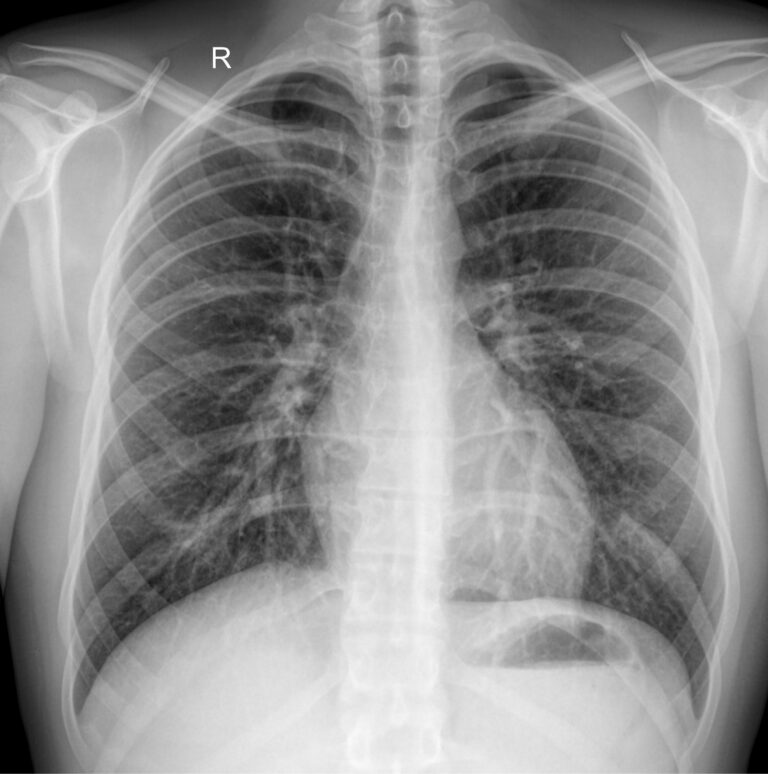

Снимок грудной клетки используют, чтобы получить изображение расположенных здесь органов: легких и дыхательных путей, контуров сердца с сосудами, а также позвоночника и костей. Обычно для диагноза достаточно одного снимка ― в прямой проекции, когда лучи идут сзади наперед. Иногда врач назначает снимок в боковой проекции, то есть слева или справа. Это необходимо, если требуется более точно определить сегмент поражения или достоверно исключить патологический процесс. Крайне редко требуются косые проекции, но они тоже бывают.

На рентгенограмме видны следующие образования, расположенные в грудной клетке:

• Мягкие ткани: грудные мышцы, кожные складки;

• Костный скелет: ребра, ключицы, грудина, нечетко ― позвонки, в пожилом возрасте ― хрящи;

• Легочные поля: определяются их прозрачность, симметричность, легочный рисунок;

• Корни легких: топография, форма, структура, ширина;

• Средостение: положение сердца и сосудов, формирующих его дуги;

• Купол диафрагмы: четкость, местонахождение;

• Синусы: свободные или заполненные.